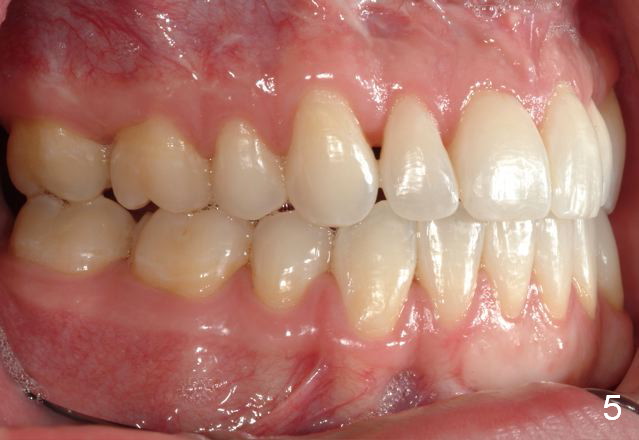

Final photos are taken on 03/23/2016. Mid face deficiency improved, now just a hint (Fig.3). Before (Fig.4,10) and after (Fig.5-9) occlusal adjustment of the canines.